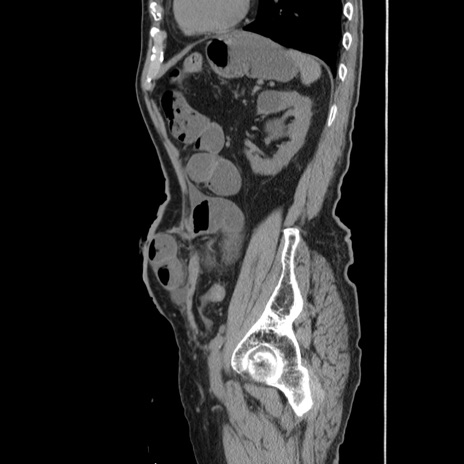

症例24(矢状断像)

【症例】80歳代男性

【主訴】左側腹部痛、嘔吐

【現病歴】本日早朝より左腹部に痛みあり。昼頃嘔吐認めたため、救急要請。

【既往歴】直腸癌(Mile手術)、胆摘

【身体所見】意識清明、BT 35.9℃、BP 221/93mmHg、SpO2 97%(RA) 、腹部:左ストーマ周囲に限局性の腹部膨隆あり。 膨隆部自発痛・圧痛あり・軟。

【データ】WBC 7700、CRP 0.09